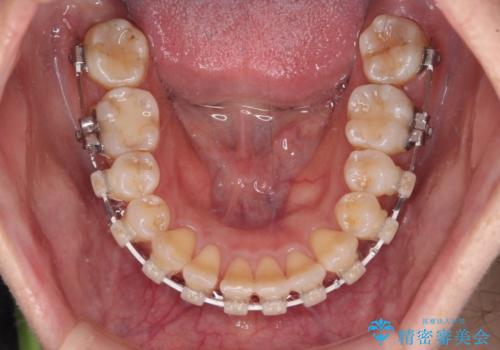

気になる八重歯 ワイヤー装置での非抜歯矯正

- 上顎の八重歯と全体的なデコボコを気にして来院された患者様です。

口元の突出感はなかったため非抜歯矯正での対応となりますが、八重歯を改善する際に上顎前歯が前突する可能性があったため、上顎臼歯部にアンカースクリューを使用して、歯列が前方に転位しないようにすることとしました。

また舌のトレーニングを行うことで、上顎前歯の突出予防や上下前歯に隙間ができなくなるようにしました。

ワイヤー矯正でもインビザラインでも対応可能でしたが、上顎歯列が前方位であるときには、ワイヤー矯正の方がより良い仕上がりとなる可能性が高いため、ワイヤー矯正をおすすめいたしました。